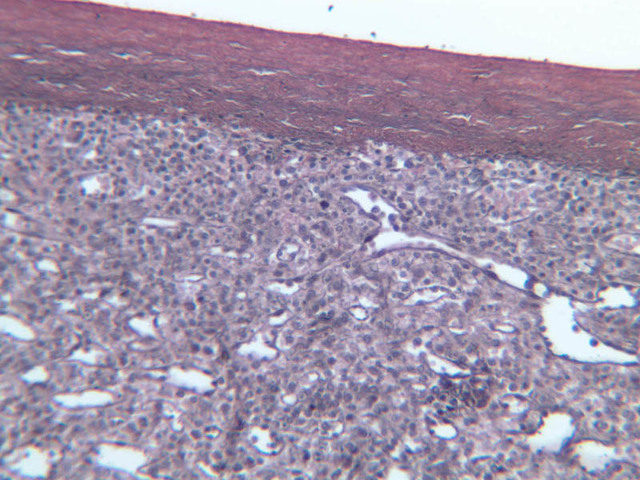

Examine slides A-43 through A-46 (A-43, H&E [2.5x, 10x, 20x]; A-44, H&E [10x, 20x, 40x]; A-46, H&E [2.5x-labeled, 10x, 20x-labeled, 40x]). Slides A-44 and [[http://www.medicalhistology.us/wiki/bin/viewfile/Main/ThymusImages?rev=1;filename=a45_hassall_corpuscle_medulla_infant_thymus_2x.jpg][A- 45]] are from infants and slide A-46 is from a young adolescent. Compare slide A-43 (adult thymus) to slide A-44 (infant thymus). First hold the slides up to the light and observe by eye that there is an increase in the amount of CT (and fat) that infiltrates the tissue with age. Now observe the differences in the appearance of the tissue at the microscopic level. Like the lymph node and spleen, the thymus is encapsulated, and the capsular connective tissue penetrates into the lymphoid tissue dividing it into compartments. But only the thymus appears lobulated. Each lobule is divided into a darker staining peripheral cortex and a lighter staining medulla. Diagnostic of the thymus are Hassall's corpuscles (A-45 [2.5x, 10x, 20x, 40x-labeled]). These are concentrically layered, eosinophilic structures found in the medulla.

Examine a section of young thymus (slides A-44, A-45). Note that it is surrounded by a thin CT capsule. Trabeculae from the capsule pass into the organ to divide the thymus incompletely into lobes (separated by thick trabeculae) and lobules (separated by thinner trabeculae). Notice that the lobules and lobes join centrally, making the parenchyma of the organ continuous throughout. Each lobule shows an outer, cortical region, densely packed with cells that are mostly lymphocytes, and a core or medullary region containing fewer cells. Lymphoid nodules with their germinal centers are absent from the thymus because it has no afferent lymphatics, i.e. this organ does not filter lymph. Examine the cortex and find large and small lymphocytes (A-44, H&E [2.5x, 10x, 20x, 40x] [2.5x, 10x, 20x, 40x]; A-45, H&E [10x, 20x, 40x] [2.5x, 10x, 20x, 40x] [2.5x, 10x, 20x, 40x]). Look for mitotic figures in the thymic cortex; these are lymphoblasts. Also try to discern large cells with acidophilic cytoplasm and large nuclei interspersed among the lymphocytes. These are the epithelioreticular cells. Now look at the medullary region where lymphocytes are sparser (A-44, H&E [10x, 20x, 40x]; A-45, H&E [2.5x, 10x, 20x, 40x-labeled] [10x, 20x, 40x]). Epithelioreticular cells are more readily apparent. Unlike the reticular cells in other lymphatic organs which are of mesenchymal descent, these reticular cells arise from epithelium of the pharyngeal pouches. Like other epithelial cells, thymic reticular cells are joined by desmosomes. In the thymus, the epithelioreticular cells form a cellular reticulum that supports the thymocytes.

Scattered randomly in the medullary tissue are acidophilic structures whose cells are concentrically arranged around an amorphous core. These are the thymic or Hassall's corpuscles. Hassall's corpuscles vary in size and appearance and are comprised of degenerated reticular cells that contain keratohyalin granules and keratin. No known function has been assigned to them.